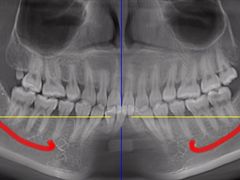

• 牙博士口腔品牌连锁(杨浦店)

• -牙博士口腔品牌连锁(杨浦店)